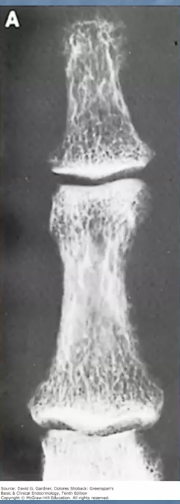

Quelles sont les signes d’hyperparathyroïdie primaire à l’imagerie?

Radiographie des os longs : Osteitis fibrosa cystica

⇒

Ostéodensitométrie : ostéoporose